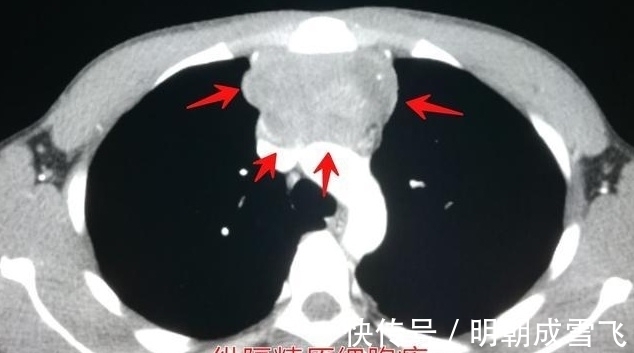

文章插图

这是一位宫颈癌4期的女性病人,44岁,进行性气短,确诊为肿瘤血栓性微血管病,病人短时间内进展恶化了。

通过尸检结果显示,癌症患者PTTM患病率为0.9~3.3%,甚至有时候也可以见于早期癌症病人。